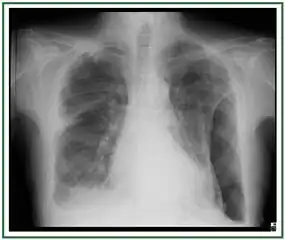

CXR of an individual affected by fibrothorax (consequence of tuberculosis)

Extensive left-sided fibrothorax

Chest radiograph displaying inhomogeneous opacification of the left half of the chest that is fibrothorax

A fibrothorax can typically be diagnosed by taking an appropriate medical history in combination with the use of appropriate imaging techniques such as a plain chest X-ray or CT scan.[3] These imaging techniques can detect fibrothorax and pleural thickening that surround the lungs.[7] The presence of a thickened peel with or without calcification are common features of fibrothorax when imaged.[3] CT scans can more readily differentiate whether pleural thickening is due to extra fat deposition or true pleural thickening than X-rays.[3]

If a fibrothorax is severe, the thickening may restrict the lung on the affected side causing a loss of lung volume.[7] Additionally, the mediastinum may be physically shifted toward the affected side.[3] A reduction in the size of one side of the chest (hemithorax) on an X-ray or CT scan of the chest suggests chronic scarring.[6] Signs of the underlying disease causing the fibrothorax are also occasionally seen on the X-ray.[6] A CT scan may show features similar to those seen on a plain X-ray.[7] Lung function testing typically demonstrates findings consistent with restrictive lung disease.[6]